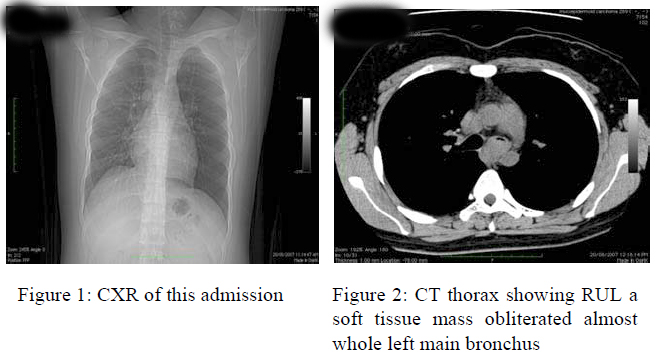

Case History

A 20 years-old never smoked man was diagnosed to have asthma in 2005 with infrequent attack and no prior hospitalization history. He was admitted for on and off haemoptysis since 2004. There was no constitutional symptom. Physical examination, including chest, was unremarkable. Previous CXR reports (in Oct 2004, Jan 2005, Nov 2005, Jun 2006 and May 2007) and this episode (Fig.1) were normal. Blood tests were essentially normal. Sputum for acid-fast bacilli was negative. He was given a course of Augmentin and there was no recurrence of haemoptysis during hospital stay. Contrast computed tomography (CT) of thorax showed a contrast enhanced 2.3cm soft tissue mass in the left main bronchus (LMB); lungs are clear and there was no lymphadenopathy (Fig 2). Bronchoscopy revealed an irregular mass at the left distal trachea extending to and obstructing LMB. The patient was transferred to cardiothoracic unit for further management subsequently. Emergency rigid bronchoscopy was performed for cored excision of the vascular tumour which resulted in massive bleeding; and Dumon stent was inserted to bypass obstruction.